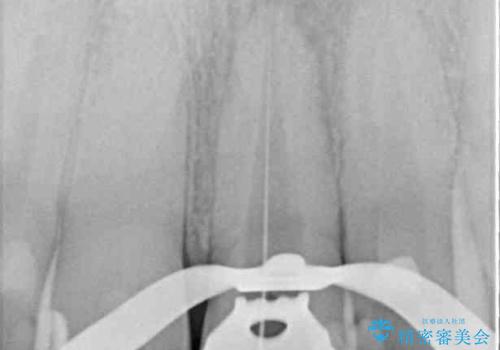

- 前歯が変色してしまったとのことで来院された患者様です。

変色が気になっていたものの痛みがなかったので看過していましたが、歯肉が腫れることが頻回となったため来院されました。

歯髄は既に壊死していたため、根管治療を行い、その後オールセラミッククラウンにて補綴することとしました。